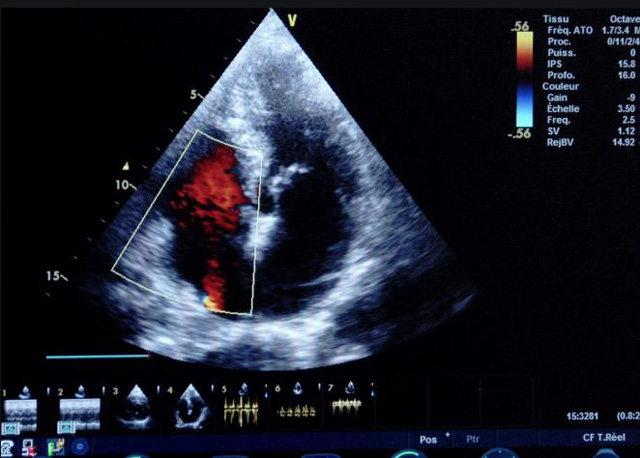

二、彩色室壁运动分析

(一)基本原理彩色室璧运动分析,从整体散射数据中识别心内膜边界,并与前一帧彩色不同,心脏收缩或舒张期开始到结束时心内膜的全部过程。每一次顺序显示结束后,原来的彩色自动消失,以便进入下一个显示过程。其结果是获得对应于每一个心动周期的彩色显示,描绘特定周期内室壁运动的时间运动轨迹。

(二)操作步骤根据背向散射数据中将心内膜运动的位移过程分类为组织或血液的原理,边缘检测跟踪心内膜和血液的界面。橙色表示收缩期的开始,收缩期不同时相逐帧显示色彩均叠加在收缩末期最后一帧图像中。检查时,可按以下步骤进行:

①显示较为理想的二维图像,常用切面有心尖四腔心、二腔心、左心室长轴和左心室乳头肌水平短轴切面。

②启动AQ系统,启动后适当地调节增益补偿,显示心内膜。

③启动CK系统,启动后划定感兴趣区域。同时记录的心动图R波顶点为舒张末期,T波终点为收缩末期,显示RT间期的CK彩阶图,连续记录3~ 5个心动周期。

④对所获图像和数据进行分析和计算。

(三)检测节段性室壁运动异常,研究冠心病患者左心室功能和分析局部室壁运动过程中。测量每一节段室壁的运动量,运动正常的节段彩带色彩均匀层次光整。运动减弱的节段,厚度薄层次不全。心内膜位移幅度和速度均减低。心内膜位移幅度和速度甚低或难以测得。正常的多层彩带消失,呈现红色色带,心内膜位移呈负向,幅度和速度亦减低。急性心肌梗死的患者中可用于识别存活心肌抑或坏死心肌。多巴酚丁胺负荷试验存活心肌的心内膜位移幅度增高,停药后即消失,而坏死心肌则无上述表现。实时检查冠心病的节段性室壁运动异常,有时候通过发现局部心肌运动的时相异常,对于心脏传导障碍的诊断也可能有帮助。